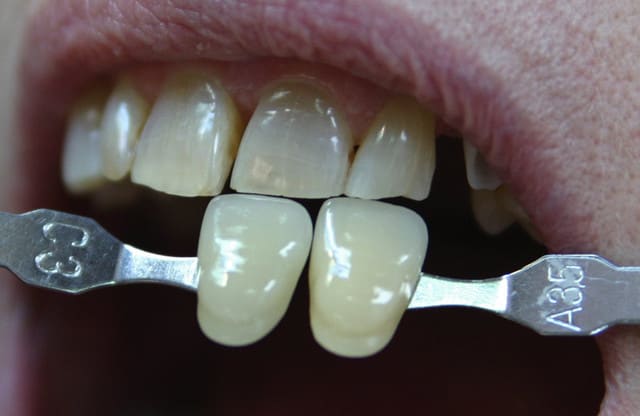

Img 5830 sx42wd - Eugenol

Img 1173 tih5r1 - Eugenol

tres belle photos.....avec ou sans flash annulaire??

merci!

la premiere etant une prise de teinte, je l' ai faite en lumière naturele, la seconde a ete faite sous scialytique. je dois recevoir mon flash annulaire dans 10 jours (le sigma...360 euro "seulement") pour ce qui est du reste, c' est un 10D avec un tamron 28/75....donc, pour ceux qui prendront un 20D avec une focale fixe et le flash annulaire d' emblée, le résultat sera plus piqué. (en fait, je n' avais pas assez d' argent pour acheter tout d' emblee il y a 15 mois...) ...mais j' apprecie mon choix un peu plus chanque jour!